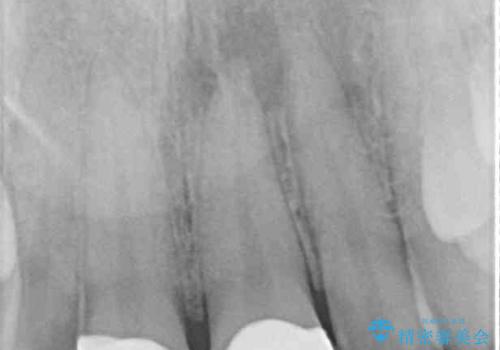

術後の経過は良好でしたが、レントゲン写真にて神経が失活している時に認められる透過像のようなものが見られました。

神経の反応はあるので失活していないようですが、時間が経過すると衝撃による失活が起こることもあるため、定期的な経過観察が必要です。